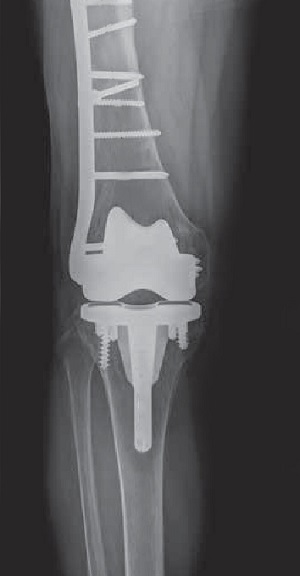

- Revision Prosthesis: When there is a loosening of the prosthesis, the whole implant will usually have to be surgically removed and replaced with a hinged knee prosthesis, which can be considered a salvage device that provides better stability to the knee.